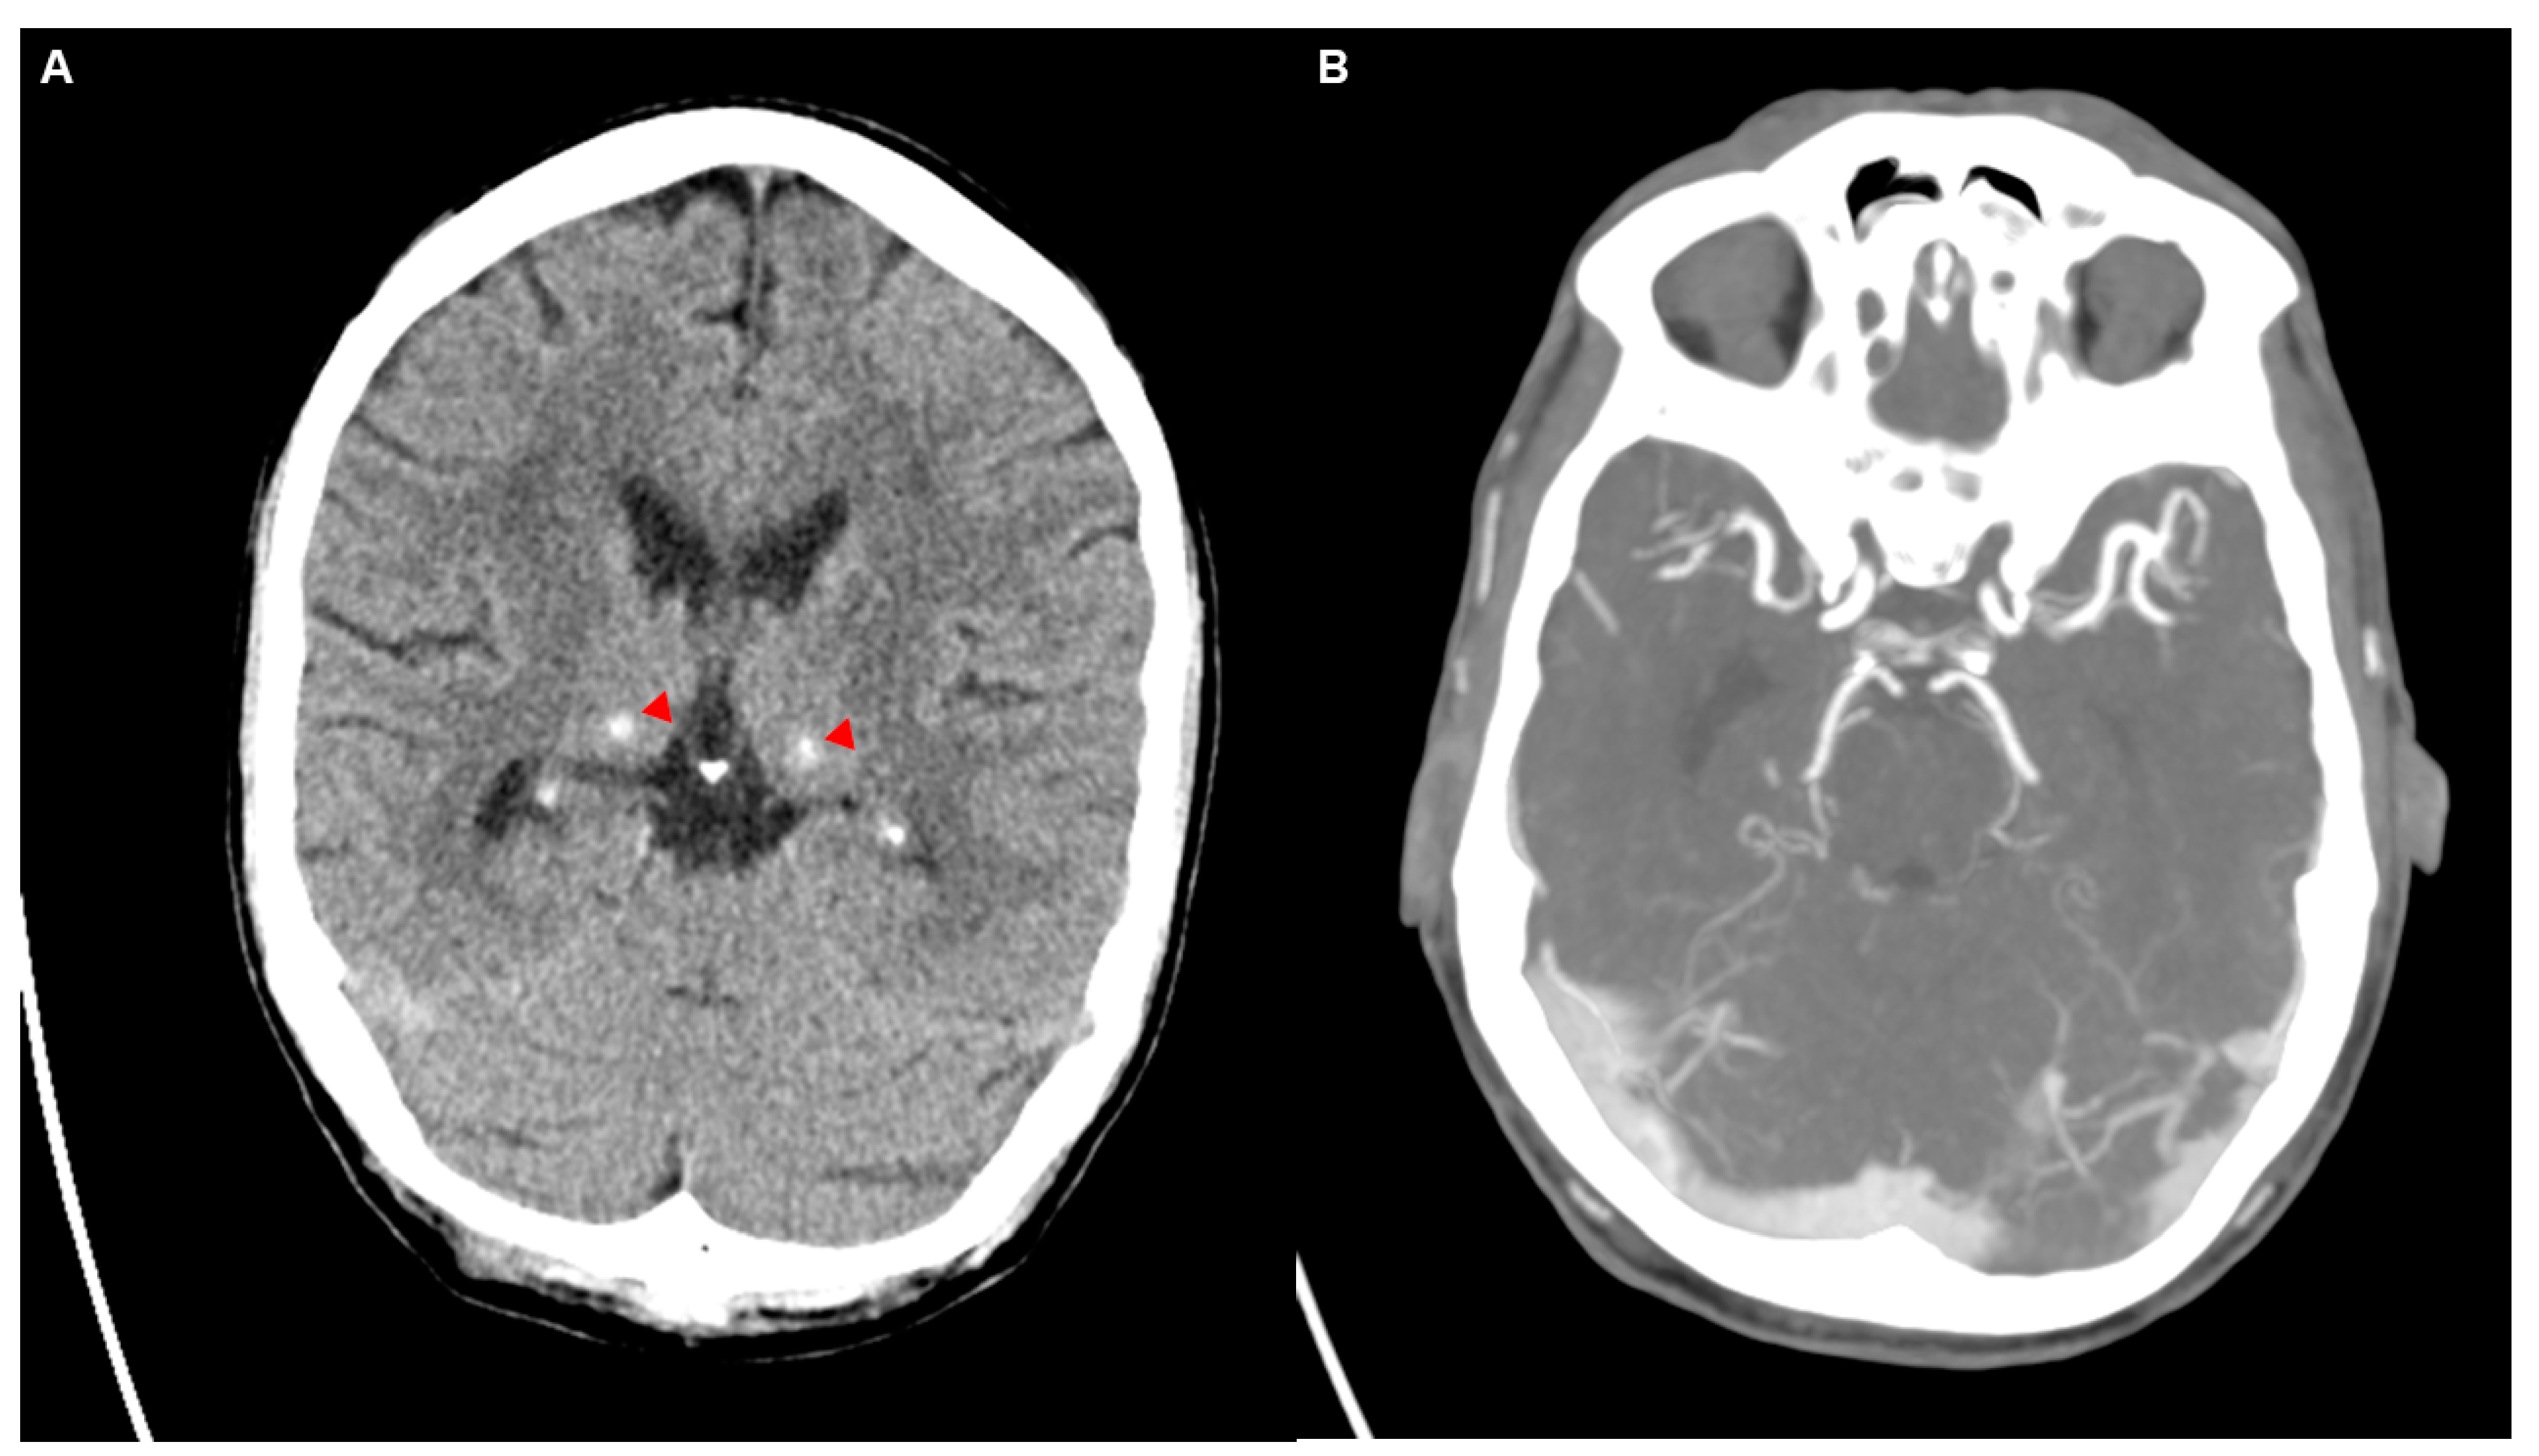

Figure 2.

The initial non-contrast CT scan of the head (A) revealed cerebrospinal fluid spaces that were age-appropriate, with no evidence of mass effect or intracranial hemorrhage. There were no signs of acute ischemic changes. Hyperdensities observed bilaterally in the thalami were consistent with calcifications, which were newly noted compared to prior imaging from 2022 (two years before). Additionally, defects that were previously observed in the right temporal lobe on imaging two years earlier were noted again, accompanied by ex vacuo dilation of the right temporal horn of the lateral ventricle. The calcifications of the basal ganglia, although newly observed, were considered incidental and had no clinical significance, consistent with previous reports of age-related or physiological calcifications in the basal ganglia and thalamus [4]. A CT angiography (CTA) (B) of the extra- and intracranial vessels in a mixed arterial and venous phase. There was a calcified plaque in the left vertebral artery, besides that the CTA showed normal arterial and venous structures without any evidence of vascular malformations, stenoses, or aneurysms. There are no signs of thrombosis or other vascular abnormalities, with intact and well-defined vessels throughout the visible cerebral vasculature.

We report the clinical course of a 59-year-old Caucasian man with poorly controlled type 2 diabetes (HbA1c 16.8%). The patient initially presented with a unilateral headache and left-sided facial numbness as well as diffuse soft tissue swelling of the face, particularly around the left orbit (Figure 1A–C). The symptoms began approximately 3–4 days before the initial presentation at the emergency department of an external clinic, where the patient was seen due to an acute and severe exacerbation of the headache. An initial computed tomography (CT) with angiography (CTA) was performed, which was unremarkable regarding brain parenchyma, aside from newly noted calcification in the basal ganglia compared to prior imaging two years before (Figure 2A). Subsequent CTA, performed with a mixed arterial and venous phase (Figure 2B), demonstrated intracranial and supra-aortic arteries without significant stenosis or occlusion. A finding was a stenosis at the origin of the left vertebral artery, attributed to a calcified plaque. The scan also revealed several contrast-enhancing lymph nodes, up to 9 mm in size, bilaterally in the neck, which were described as unspecific. Importantly, there was no evidence of sinus or cerebral venous thrombosis.